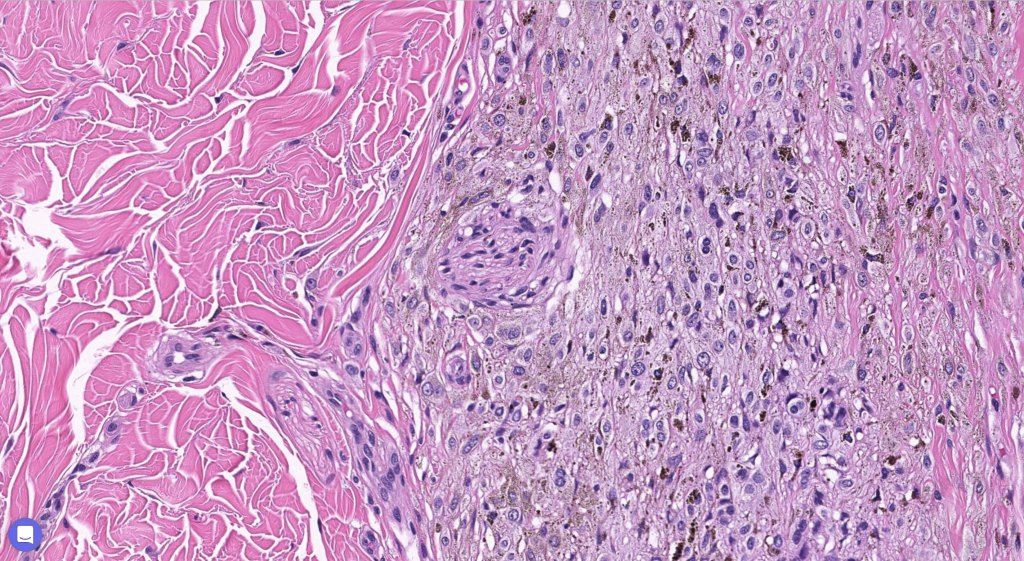

Cellular blue nevus

This uncommon most often devlops on the buttocks, sacrococcygeal region & distal extremities although it may be seen at just about any site. It shows a predilection for females and is diagnosed most often in the 2nd-4th decade. It presents as a blue-black/ or black nodule measuring 1-2 cm in dianeter. Similar to common blue nevus, the cellular variant can be encountered in a wide range of non-cutaneous locations.

Histological features

•Most characteristic is the dumbbell silhouette although a plague morphology may also be encountered

•Admixture of spindle cells, pigmented bipolar or dendritic cells & melanophages

•Cytoplasm is pale and nuclei are small with inconspicuous nucleoli

•An alveolar pattern is characteristic particularly with clear cell nodules

•Stromal fibrosis, myxoid change, vascular hyalinization with cyst formation are often seen

•Some tumors are composed spindle cells in a fascicular or neuronevoid pattern